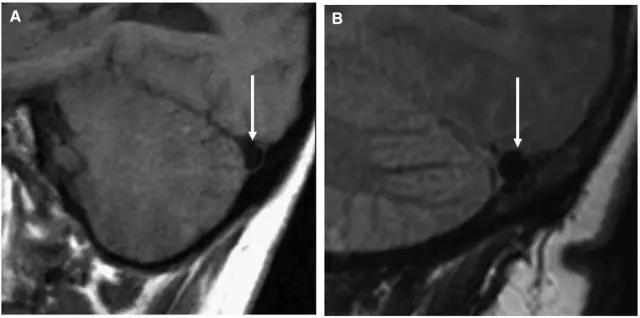

患者,男,40岁;因不明原因反复头痛并加重2月,于2017年4月21日当地医院头颅CT、MRI提示:双侧额颞顶部慢性硬膜下血肿收住院(图1)。并于4月24日行“左侧慢性硬膜下血肿钻孔引流术”。术后患者卧床、静脉补液,头痛症状有所缓解。复查头颅CT显示左侧血肿较前减少,但右侧稍增大(图2)。

图1. 第一次术前CT及MRI显示双侧慢性硬膜下血肿,中线稍右偏。

图2. 左侧慢性硬膜下血肿钻孔引流术后1天复查头颅CT,显示左侧硬膜下血肿较术前减少。